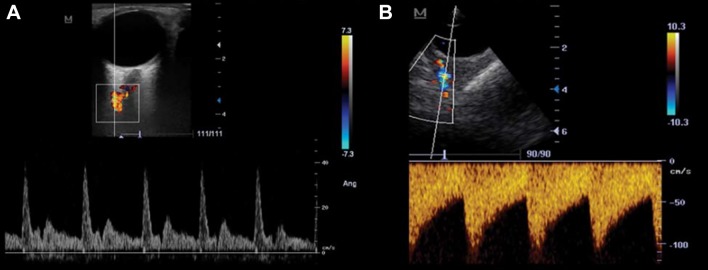

The transorbitary window shows the anechoic globe and the echogenic retrobulbar area. On color Doppler, approximately at a depth of 40 mm, the ophthalmic artery (coded red) crosses the optic nerve (Fig. 13). At a depth of 80 mm, the carotid siphon can be investigated, as in TCD. The utility of this window also lies in the possibility of measuring the optic nerve sheath diameter (ONSD) for non-invasive assessment of intracranial pressure [15].

Fig. 13.

TCCS from a transorbital view. a Linear probe. Note the normal ophthalmic artery flow toward the transducer in both color and spectral Doppler. b Phased array probe. Note the retrograde ophthalmic artery flow, both in color and spectral Doppler (negative in scale at right), away from transducer. This flow profile indicates near or occlusion of ipsilateral internal carotid artery and compensatory flow through collaterals of the ipsilateral external carotid artery

(a Reproduced with permission from [25])